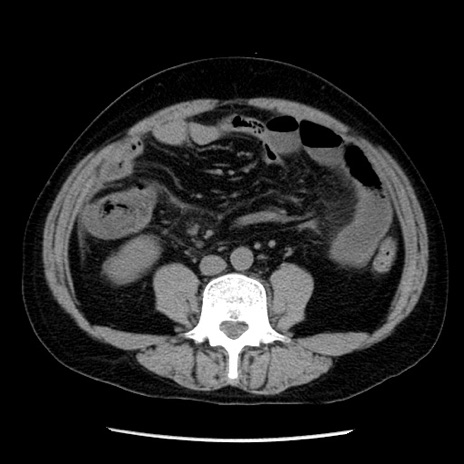

症例29(横断像)

【症例】40歳代男性

【現病歴】2日前から胃痛あり。徐々に周期的な激痛に変化した。本日になっても激痛があるため受診。

【身体所見】意識清明、BT 38-39℃台あり、腹部:膨満、やや硬、右下腹部に圧痛あり。

【データ】WBC 8500、CRP 23.26